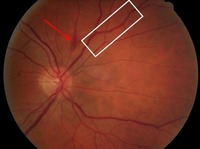

Non-proliferative diabetic retinopathy: flame haemorrhage (red arrow), venous beading (white rectangle)

Courtesy of Moorfields Photographic Archive; used with permission